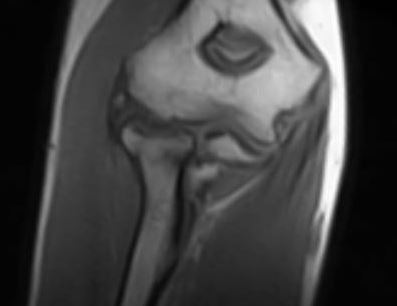

Risonanza Magnetica del gomito- Sagittale Gomito

Una volta pronto, il paziente si sdraierà supino sul lettino della risonanza con il braccio lungo il corpo e la mano leggermente allontanata dal fianco in posizione supina. È richiesta grande partecipazione e collaborazione al paziente in quanto non dovrà muovere le dita né il braccio per tutta la durata dell’esame che si aggira attorno ai 30 minuti.

Viene compresa la visualizzazione delle strutture anatomiche del gomito in generale fino a comprendere la parte finale dell’omero e la parte prossimale delle ossa radio e ulna.

Il paziente verrà quindi posizionato con il gomito al centro del magnete e di conseguenza, in linea di massima, il resto del corpo si troverà al di fuori del magnete stesso consentendo al paziente di ruotare il viso verso la parte aperta per maggiore comfort.